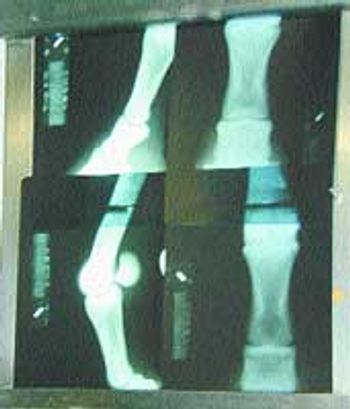

Veterinarians are commonly asked to evaluate horses for their clients and these "prepurchase" examinations often include radiographs.